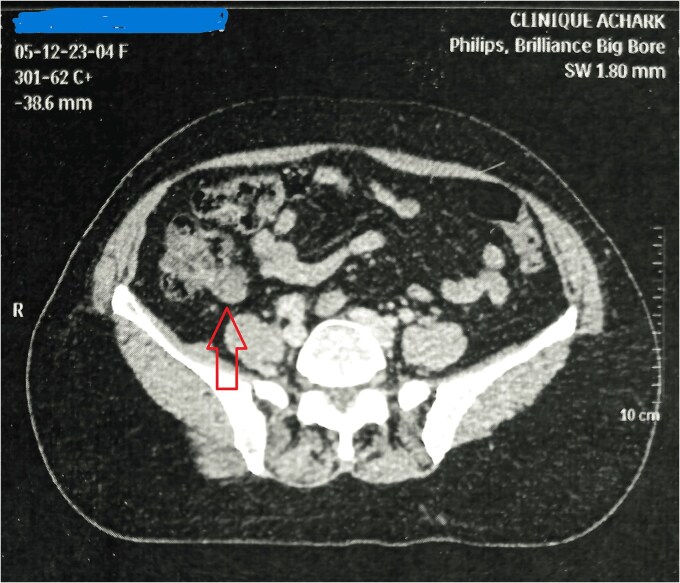

阑尾的神经内分泌肿瘤是一种罕见但具有临床意义的肿瘤,通常在外科手术或其他腹部疾病的放射检查中偶然发现。当它们与阑尾粘液囊肿(另一种罕见的实体,其特征是由于粘液积聚而导致阑尾异常扩张)合并时,这些并发表现可能会给诊断和治疗带来挑战。在这里,我们报告一个54岁的女性,以前诊断和治疗早期乳腺癌。在常规检查中,腹部超声显示阑尾区域有可疑肿块。患者接受了腹部计算机断层扫描和腹部磁共振成像,显示右下象限有一个不均匀的肿块。病人接受了阑尾切除术和肿瘤切除术。

Neuroendocrine tumors of the appendix are rare but clinically significant tumors, often discovered incidentally during surgical procedures or radiological investigations for other abdominal conditions. When they occur in association with an appendiceal mucocele, another uncommon entity characterized by abnormal dilation of the appendix due to mucus accumulation, these concurrent findings can present diagnostic and therapeutic challenges. Herein, we report the case of a 54-years-old female, previously diagnosed and treated for early-stage breast cancer. During routine surveillance, an abdominal ultrasound revealed a suspicious mass in the region of the appendix. The patient underwent abdominal computed tomography followed by abdominal magnetic resonance imaging, which demonstrated a heterogeneous mass in the right lower quadrant. The patient underwent an appendectomy and resection of the tumor.